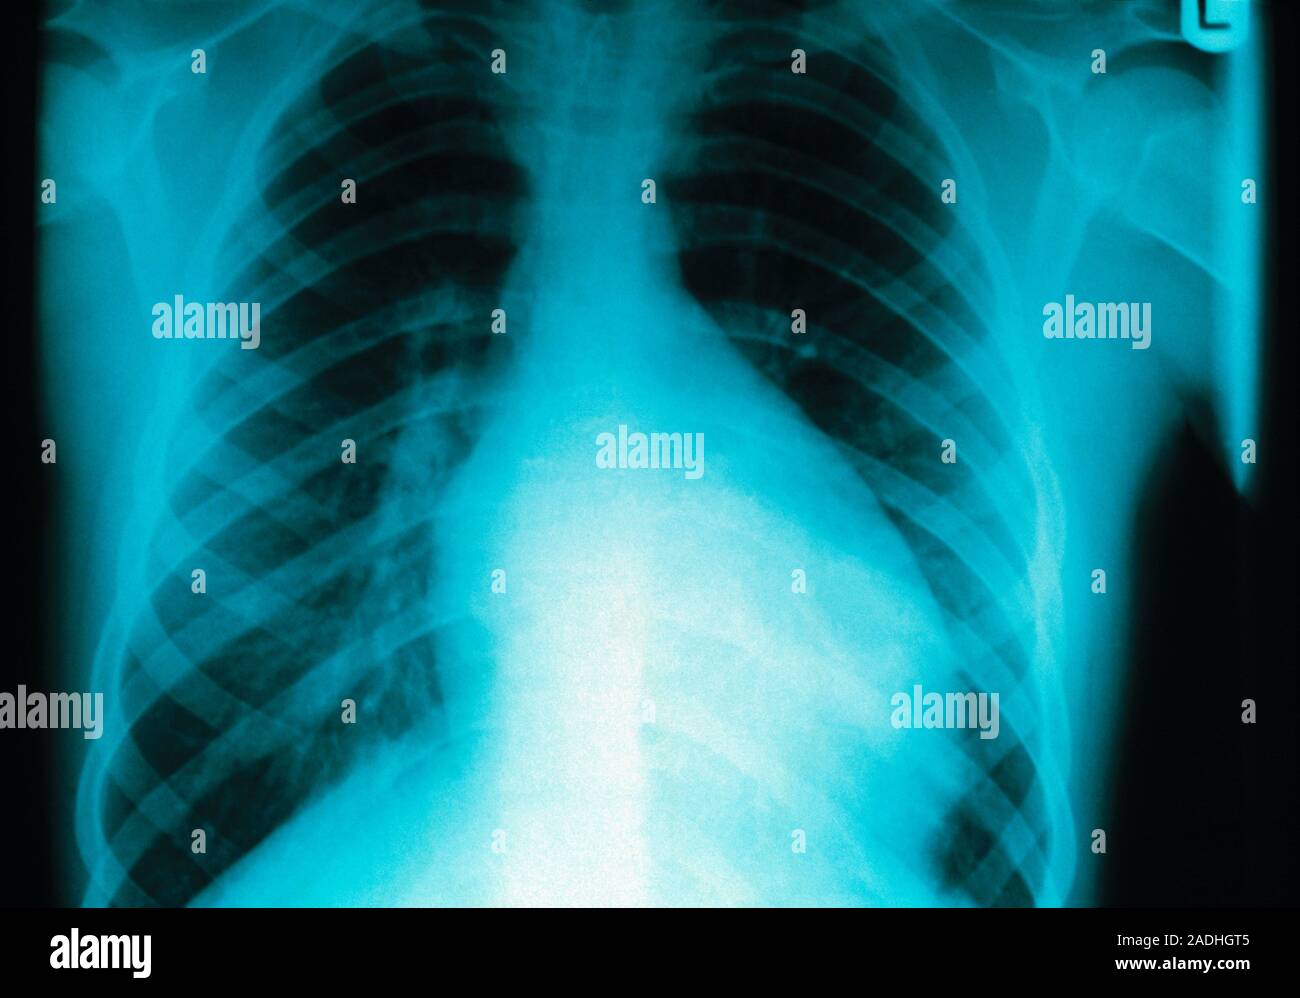

Figure 1. Chest Xray 2 days prior to presentation Myocarditis

Does A Chest X Ray Show Myocarditis . Occasionally a heart, or myocardial biopsy is. chest pain may occur, in a variety of typical and atypical presentations. these cells release chemicals. myocarditis can lead to heart failure, rhythm disturbances, or rarely cardiogenic shock (a condition that occurs when your heart suddenly cannot pump. A normal ecg does not exclude myocarditis. Will often be normal in myocarditis, but it may show features consistent with heart failure (alveolar oedema, bilateral pleural effusions,.